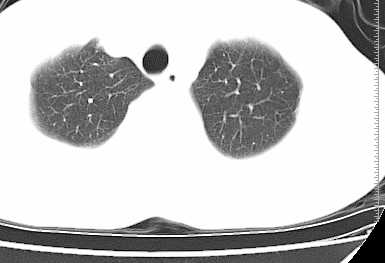

二周前患者无明显诱因出现咳嗽,多为刺激性干嗽,无咯血,伴心悸,低热,夜间无明显盗汗,消瘦明显

年龄?左侧胸腔中量积液,左下肺见有较多斑片状和大片状影,伴有支气管充气征,考虑:1、左下肺炎;2、结核。肿瘤可以基本排除。

左下肺见有较多斑片状和大片状影,支气管通畅,左侧胸腔积液,考虑:左下肺炎伴胸腔积液

左侧中量胸腔积液伴左肺下叶肺膨胀不全、上肺外围多个小囊样腺泡样病灶。考虑化脓炎症。

患者刺激性干嗽,无咯血,伴心悸,低热,夜间无明显盗汗,消瘦明显,左侧中量胸腔积液伴左肺下叶肺膨胀不全、上肺外围多个小斑片病灶。考虑肺结核可能性大。

左肺舌叶及下叶见斑片状,大片状高密度影并相应处胸膜及心包不规则增厚,左肺下叶膨胀不全。右肺未见异常,双肺段以上支气管通畅。纵隔左移,其内未见明显肿大淋巴结。左侧胸腔积液。

1.考虑:左肺化脓性炎症。2.左侧胸腔积液(中等量)。3.心包炎症。